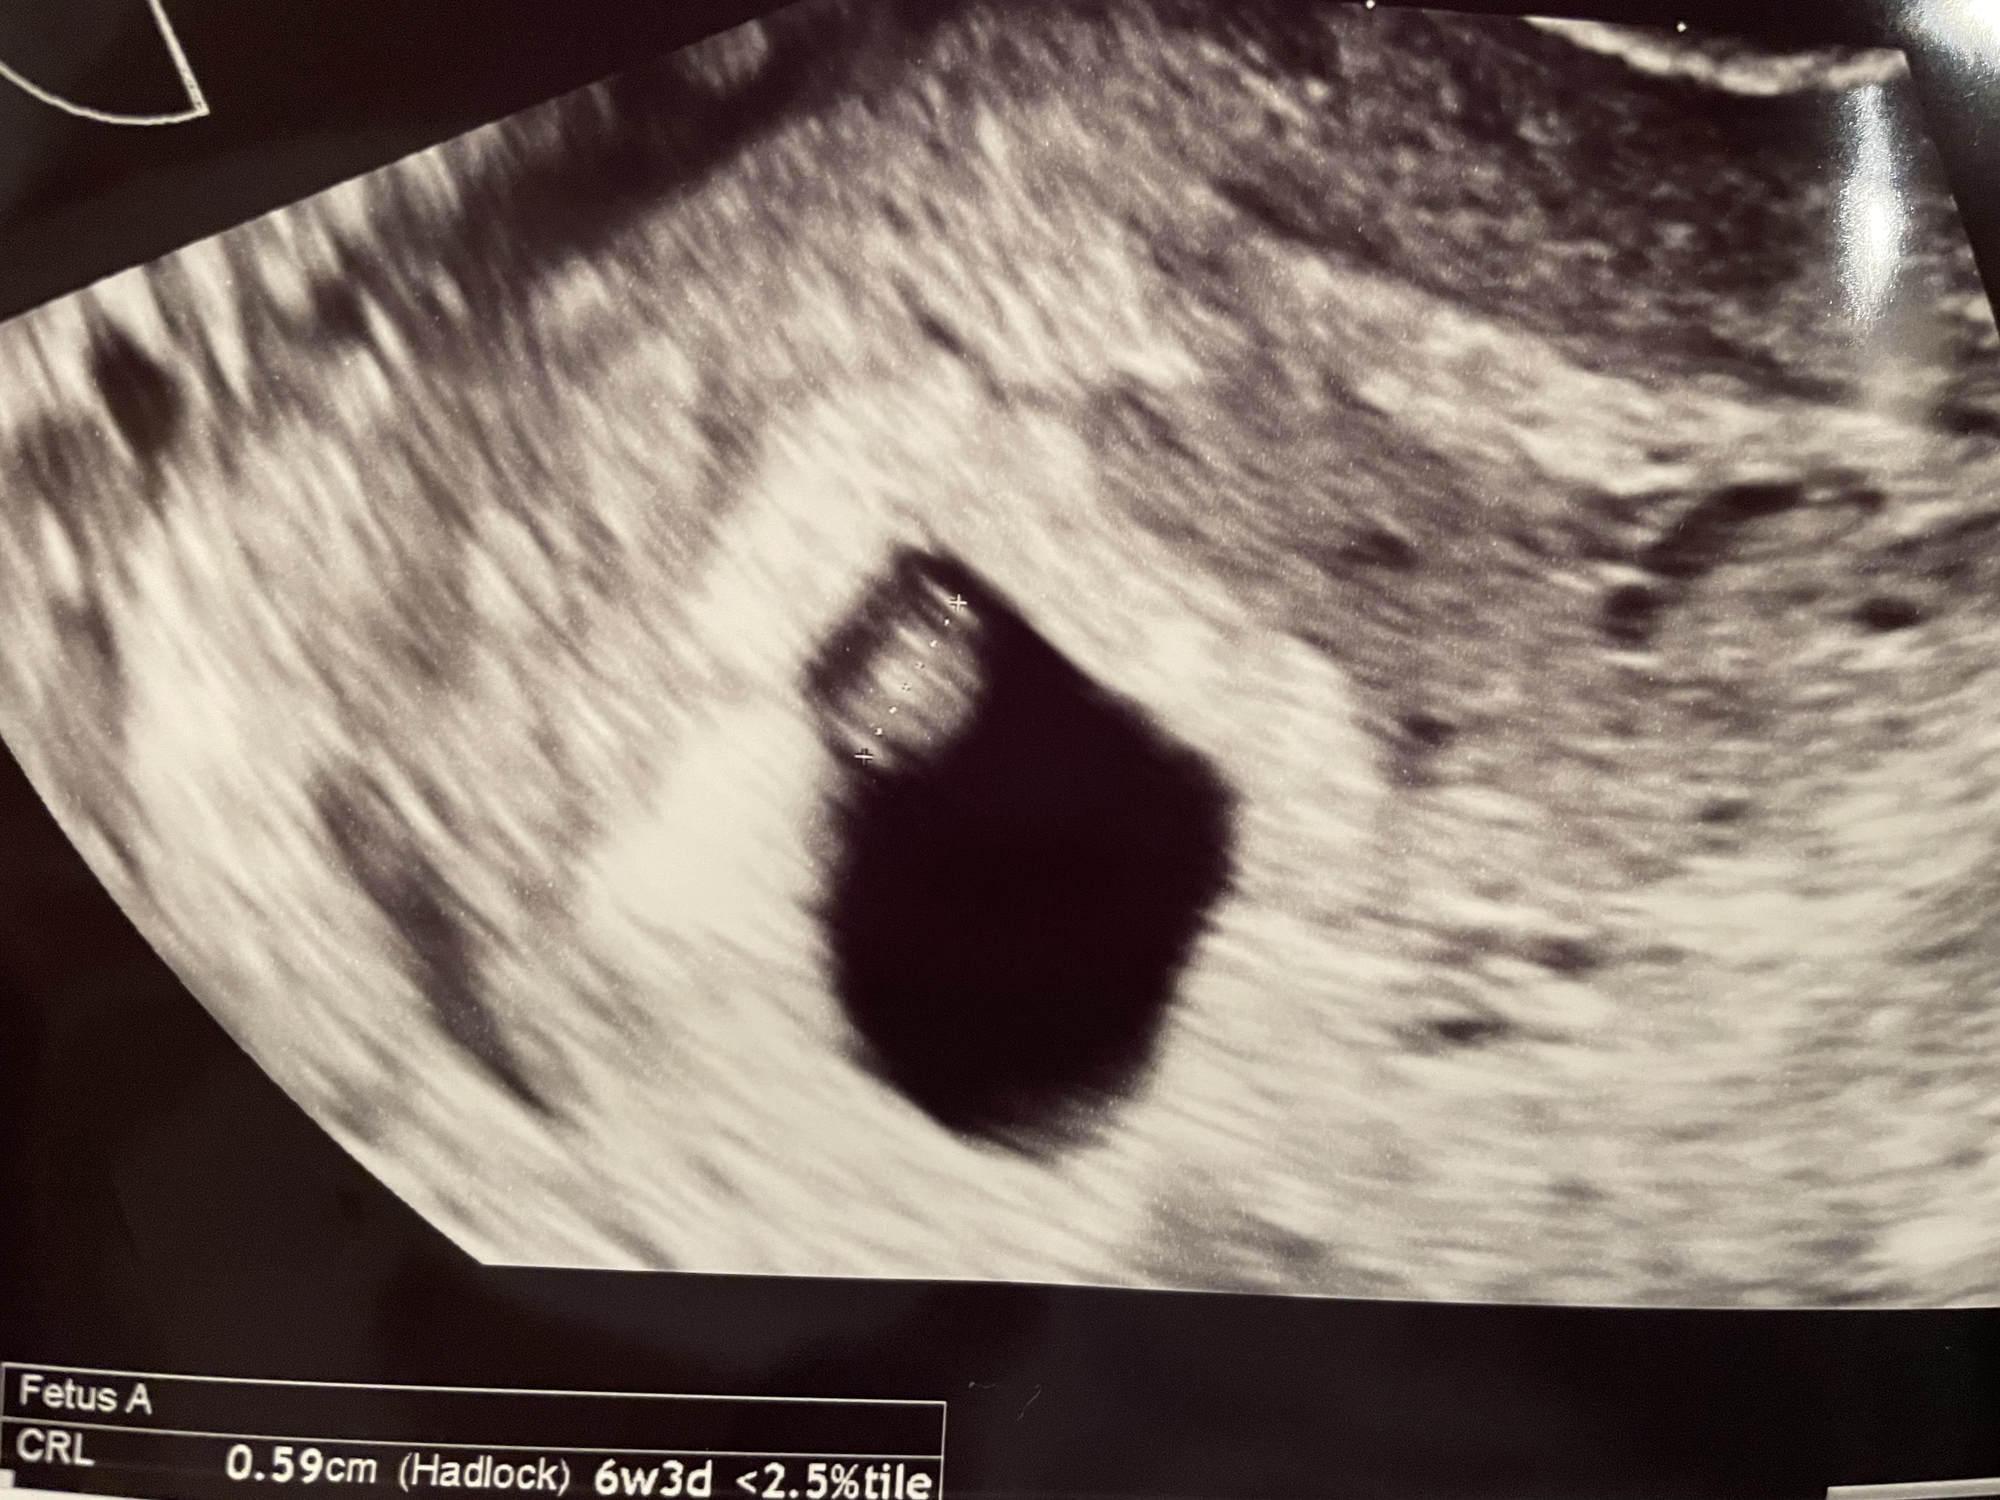

After 5 losses, doc had me in at 6 weeks 1 day for early scan! First time seeing a heartbeat❤️ he said it looked great at 126 bpm! I have my 8 week scan in about a week and I cannot wait to see my lil bean again!